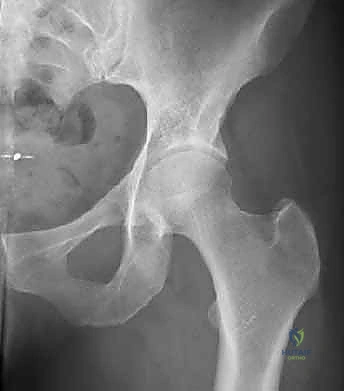

- التصوير بالأشعة السينية (X-rays): صور دقيقة بوضعيات خاصة (AP Pelvis, Dunn view, Cross-table lateral) لقياس زوايا محددة مثل زاوية ألفا (Alpha Angle) التي تؤكد وجود تشوه "كام"، وعلامة التقاطع (Crossover Sign) التي تؤكد وجود تشوه "بنسر".

صورة شعاعية قبل التدخل الجراحي توضح التشوه العظمي بوضوح.